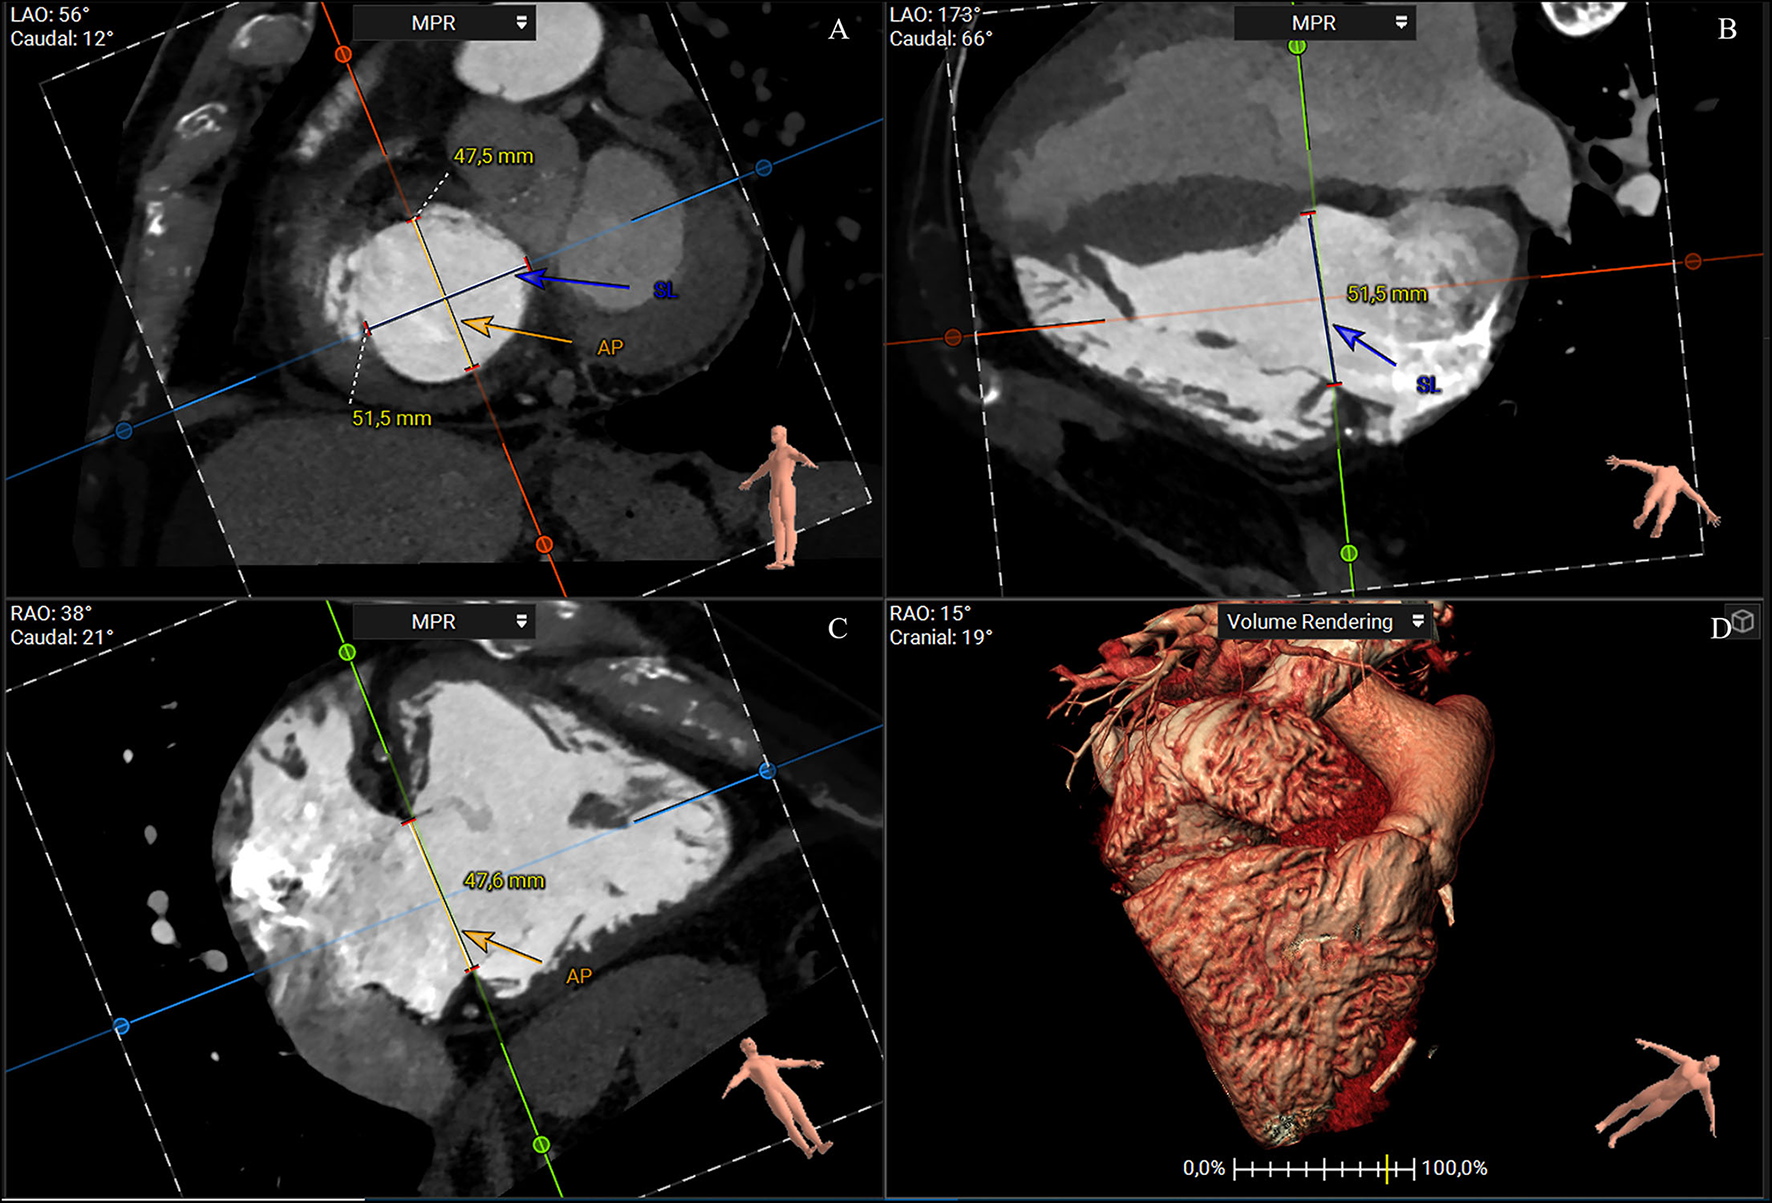

A short-axis plane can be reconstructed on the annular level using multiplanar reconstruction starting from RV two- and four-chamber views. Cross-sectional area, perimeter, septolateral, and AP diameters can be obtained with excellent intra- and interobserver reproducibility (25). The cross-sectional area and perimeter can be assessed by planimetry or using semiautomated software (32–34). The septal–lateral diameter is the maximal distance in septal to the lateral direction and coincides with the annulus measurement in the four-chamber view. The AP diameter is orthogonal to the septal–lateral one. It coincides with the measurement in the two-chamber view with the anterior and posterior wall visualization and the respective leaflets (Figure 3). Because of the dynamic variability in annular size, dimensions should be achieved both in end-systole and mid-diastole. Moreover, since the typical non-planar saddle-shaped structure of the tricuspid annulus, the 2D approach for obtaining measurements does not accurately address the complex annular geometry. Therefore, a dedicated 3D semiautomated software can be valuable in overcoming this disadvantage (Figure 4) (32–34).

Figure 3

CT multiplanar reconstruction showing the short-axis plane at the annular level (A), the derived four chamber (B), two chamber (C), and volume rendering of the right chambers (D). The annulus septal-lateral diameter is measured in septal to lateral direction (A, blue line) and coincides with the annulus measurement in the four-chamber view (B). The anteroposterior diameter is orthogonal at the previous one (A, orange), and coincides with the measurement in the two-chamber view (C) (3mensio Structural Heart; Pie Medical Imaging, Maastricht, The Netherlands). AP, anteroposterior; SL, septal-lateral.